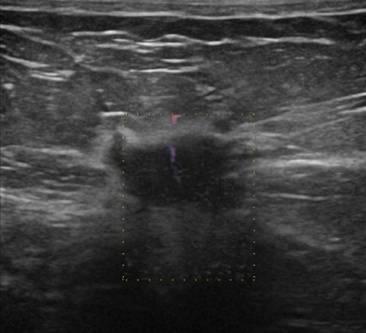

Ung thư vú

Ung thư vú - Ảnh 2

» Thông tin: Nữ giới – 56 tuổi.

» Lâm sàng: Khối tuyến vú.